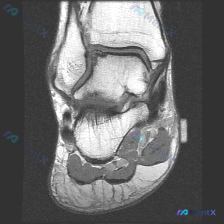

整理了一例踝关节MRI读片病例,把分析思路分享给大家,一起看看这个表现不简单的病例。 病例基本影像信息 这是一张脚踝MRI冠状位T2序列影像,可见的解剖结构包括胫骨远端、腓骨远端、距骨及部分跟骨。 核心影像异常发现 1. 骨骼: 距骨上方穹窿区域可见大范围不均匀高信号,边缘欠清晰,提示软骨下骨骨髓水...